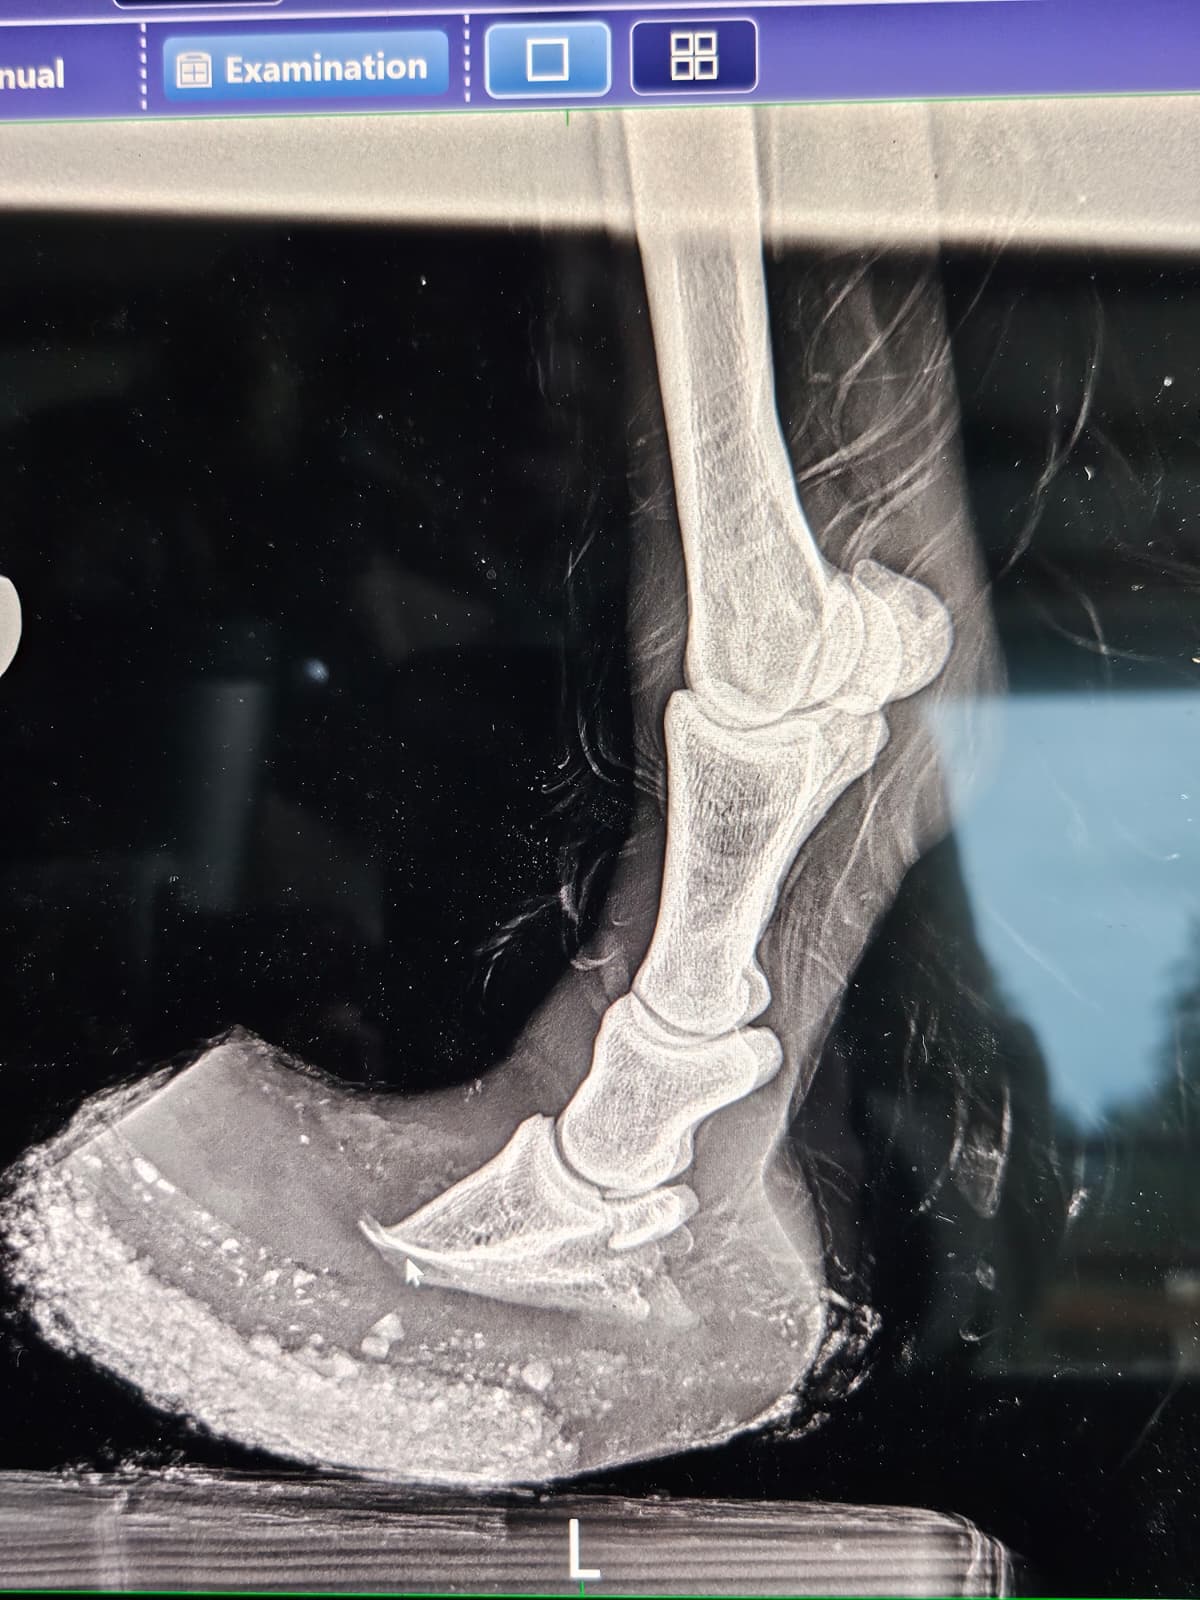

It was for our little red friend we worried the most. Hooves like hers don’t grow overnight, and the reality of what living with hooves like those does to a horse’s anatomy is at best, manageable, and at worst, unlivable. She was incredibly nervous, and required a very patient, quiet touch to allow us to sedate her for the radiographs we needed to understand what we were working with. Her small buddy accompanied her to where they had set up the x‑ray station, and stood patiently nearby as we peered under the hood.

The films revealed the depth of damage that walking on imbalanced, overgrown hooves for extended periods can do. The tips of her coffin bones were remodeling, and her hooves were severely unbalanced, with a long and deep abscess track in one of her hinds. Despite these findings, the vet was of the opinion that it might be possible to keep her and her friends comfortable with significant rehabilitation, and that all four horses were fit enough to join us back at SAFE.